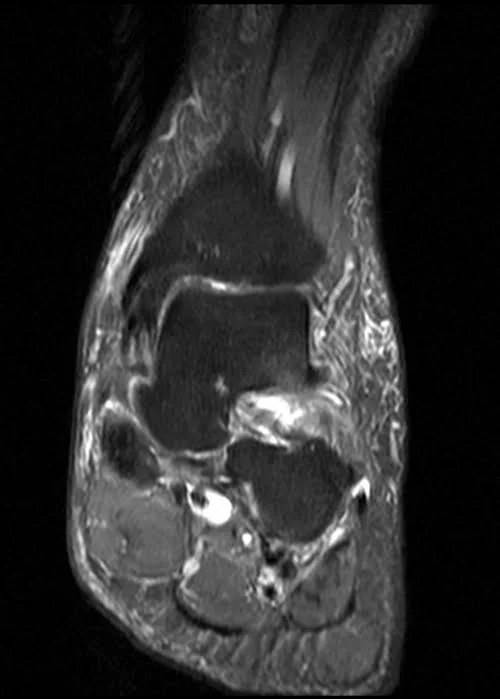

MRI ANKLE COR PD FS IMAGE 2 - MRI